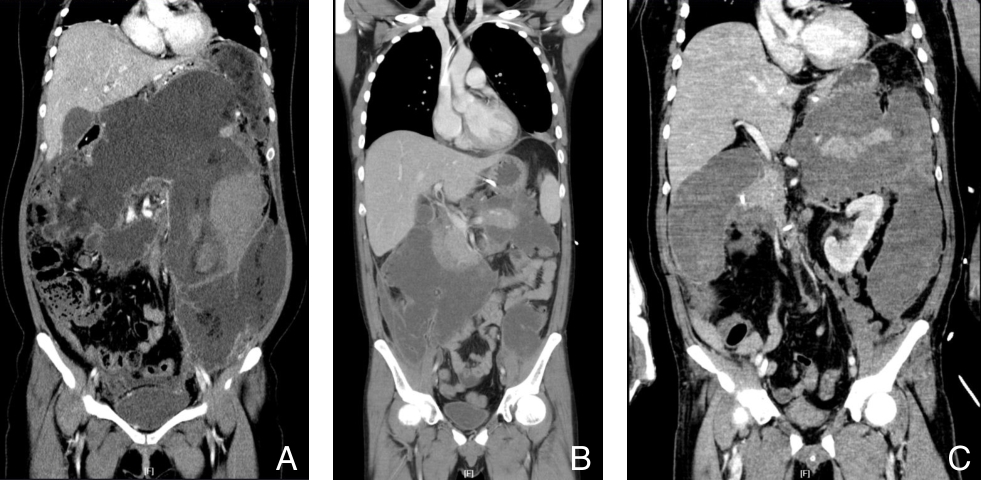

摘要:背景与目的 早发广泛性气肿型胰腺炎(EP)是一种起病急骤、进展迅速、病死率极高的感染性胰腺坏死(IPN)亚型,临床少见,相关研究有限。本研究旨在分析其临床特征、病原谱特点、治疗方式及预后,为早期识别与干预提供依据。方法 回顾性分析2010年1月—2023年10月中南大学湘雅医院305例IPN患者的临床资料。根据影像学特征筛选出起病2周内胰腺或胰周坏死面积≥50%、呈大片状气泡征的早发广泛性EP 8例,并与普通IPN患者进行比较,分析两组的临床特征、病原学分布、治疗策略及结局。结果 305例IPN中,早发广泛性EP占2.6%。早发广泛性EP组病死率和多器官衰竭发生率均明显高于普通IPN组(75.0% vs. 24.6%、75.0% vs. 34.7%,均P<0.05)。早发广泛性EP患者共检出15株病原微生物,主要为肺炎克雷伯菌(62.5%)和大肠埃希菌(37.5%),其中耐碳青霉烯类肠杆菌感染率明显高于普通IPN组(75.0% vs. 31.1%,P=0.015)。治疗方式以经皮穿刺置管引流为基础的升阶梯策略为主,与普通IPN组无明显差异(P=0.625)。结论 早发广泛性EP是IPN的罕见亚型,具有进展迅速、病死率高的特点。肺炎克雷伯菌和大肠埃希菌是主要致病菌,应警惕其耐药感染风险。对疑似病例应尽早影像学评估并积极干预,以改善预后。